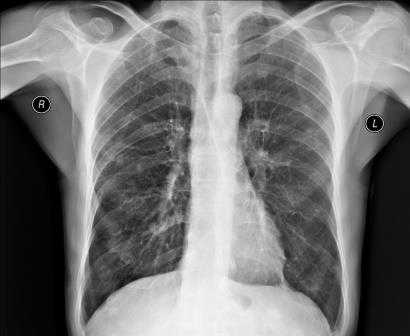

Для выявления патологических изменений сердца и оценки их влияния на сосудистое русло легких наиболее часто применяют рентгенографическое исследование грудной клетки, позволяющее получить изображение средостения, сердца и легких.

В норме на снимках, выполненных в заднепередней проекции, ширина грудной клетки по меньшей мере в 2 раза превышает поперечный размер сердца. В то же время в переднезадней проекции относительные размеры и положение сердца могут быть другими; возможно усиление тени сердца и дуги аорты. Когда исследование проводится с контрольной целью, рентгенограммы грудной клетки должны подтверждать правильное положение катетеров и водителей ритма.

Изменение формы сердца обычно заключается в увеличении левого или правого желудочка, левого предсердия или даже нескольких полостей. При увеличении левого желудочка в заднепередней проекции левая граница сердца становится круглой и выпуклой с боковым расширением в своей нижней части, а в боковой проекции определяется выбухание левого желудочка кзади. При увеличении правого желудочка в заднепередней проекции наблюдается вторичное изменение левой границы сердца за счет расширения тени легочной артерии, а в боковой - расширение тени выносящего тракта правого желудочка. При увеличении левого предсердия его плотность на рентгенограмме в заднепередней проекции увеличивается вдвое, левая граница сердца сглаживается, левый главный бронх смещается кверху. В редких случаях правая граница сердца над проекцией правого желудочка расширяется кнаружи. В боковой проекции определяется выбухание левого предсердия кзади. Начальными признаками застоя в малом круге кровообращения на снимках, сделанных в заднепередней проекции, являются расширение тени легочных вен в верхнебоковой части корней легких и сосудистые тени, расположенные горизонтально вдоль нижней части правой границы сердца. Хроническая легочная венозная гипертензия приводит к формированию рисунка по типу оленьих рогов (из расширенных верхних и нормальных или суженных нижних легочных вен). При остром отеке легких увеличение плотности в центре легочных полей может по форме напоминать бабочку. Интерстициальный отек легких может напоминать снежные хлопья на фоне легочных полей.

Рентгенография грудной клетки - это метод диагностики, позволяющий получить изображение органов грудной полости с помощью облучения рентгеновыми лучами. Различные ткани организма в зависимости от своей плотности по-разному пропускают рентгеновы лучи, а значит, по-разному отображаются на снимке (рентгенограмме).

Рентген грудной клетки дает возможность изучить костные структуры (ребра, грудину, позвоночник), легкие, плевру, бронхи и трахею, сердце и средостение, а также оценить состояние мягких тканей этой области.

Рентген (рентгенография) органов грудной клетки - это метод диагностики, использующий для визуализации органов грудной полости рентгеновское излучение. С помощью рентгена грудной клетки может быть получено изображение костных структур - ребер, грудины, позвоночника; на рентгенограммах также видны легкие, плевра, бронхи, трахея, сердце и средостение.

Рентген органов грудной клетки применяется, прежде всего, для диагностики заболеваний легких. С помощью рентгена выявляются очаги воспаления в лёгких, в том числе характерные для таких заболеваний как пневмония и туберкулёз, наличие новообразований и отёков, инородные предметы, попавшие в лёгкие. Также рентген грудной клетки используется в диагностике заболеваний сердечно-сосудистой системы (сердца, аорты) и позвоночника.

Рентгеновское излучение поглощается различными органами и частями тела по-разному. Плотные образования, например, кости, поглощают излучение сильно, в то время как мягко-тканные структуры (мышцы, жировая ткань и внутренние органы) в большей степени пропускают рентгеновские лучи через себя. В результате на рентгенограмме костная ткань выглядит белой, воздух и воздушные полости - черными, а мягкие образования получают различные оттенки серого.

При рентгенографии органов грудной клетки основная часть излучения поглощается ребрами, которые на снимке выглядят белыми или светло-серыми. Ткань легких поглощает рентгеновские лучи слабо, а поэтому на рентгенограмме получается темного цвета.